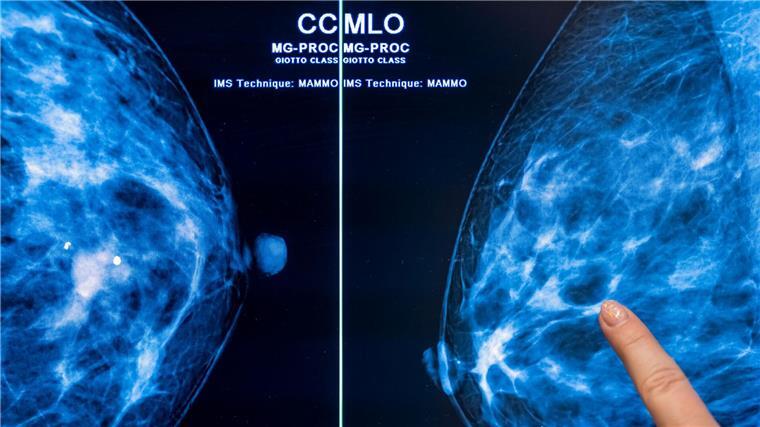

IN Niedersachsen erkranken nach Daten der Kaufmännischen Krankenkasse KKH mehr Frauen an Brustkrebs. (Symbolbild)

Foto: Hannibal Hanschke